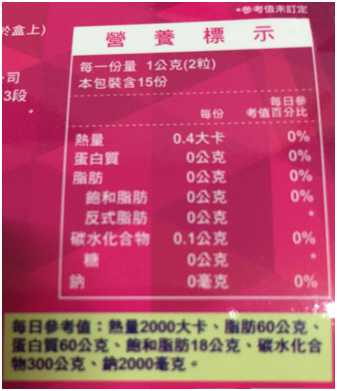

Supercut塑魔纖立塑膠囊的成分有:瓜拿那萃取粉、肉桂萃取粉、辣椒萃取物(唐辛子)、吡啶甲酸鉻、番瀉葉粉末、玉米澱粉、氧化鎂、二氧化矽。

食用方式:早晚餐前30分鐘各1粒,每日不超過2粒。(多食無益)